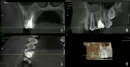

Несколько дней назад у меня откололся кусочек зуба (верхняя 6-ка), запломбированного и депульпированного два года назад. Сам зуб не болит и не беспокоит. Был сделан КТ снимок, на котором стоматолог увидела четвертый, не запломбированный канал (на фото постарался приблизить). Врач сказала, что остальные каналы тоже плохо запломбированы, что вызвало периодонтит. Нужно все вычищать и закладывать лекарство с временной пломбой, с последующей установкой постоянной пломбы. Предупредила, что возможно не получится найти четвертый канал, и тогда зуб в будущем подлежит удалению.

Есть ли смысл проводить лечение, или готовиться к удалению? На снимках видно какое-то контрастное вещество в гайморовой пазухе, это гной?

По данному снимку нельзя сказать, что есть, какой-то экссудат в гайморовой пазухе.

Зуб можно попытаться вылечить, но 100% гарантий на успех нет.